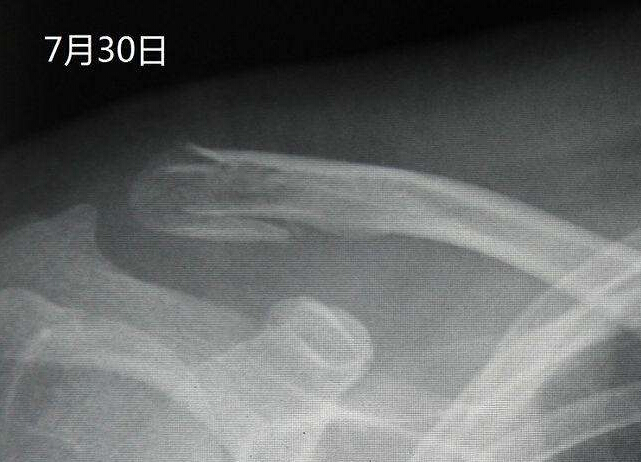

【摘要】通过拍摄X线片,可以了解骨折的部位,骨折线的走向,骨折的移位情况,骨折的类型等,为医师制定治疗方案,监测治疗结果提供依据。X线照片一般需要拍摄正位和侧位,同时应包括邻近关节,这样才能全面地反映出骨折的全貌。尽管如此,有些骨折还需要加摄特定位置才能显示骨折线,有些骨折需经1~2周后骨折处骨质吸收才能显示骨折线。

通过拍摄X线片,可以了解骨折的部位,骨折线的走向,骨折的移位情况,骨折的类型等,为医师制定治疗方案,监测治疗结果提供依据。X线照片一般需要拍摄正位和侧位,同时应包括邻近关节,这样才能全面地反映出骨折的全貌。尽管如此,有些骨折还需要加摄特定位置才能显示骨折线,有些骨折需经1~2周后骨折处骨质吸收才能显示骨折线。